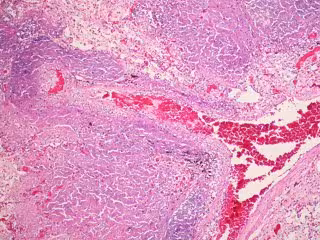

Tuberculosis

FLICKER/ PULMONARY PATHOLOGY - Archivo